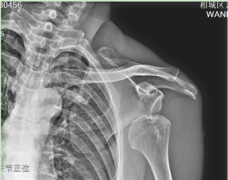

• 相城高新区:七旬老人肩关节脱位,中医科医生一招复位!

近日,喜欢锻炼的吴大爷去公园锻炼时不慎摔倒,习惯性用左手撑地,只听咔哒一声,左肩部疼痛剧烈,活动受限。吴大爷急忙来元和街道社区卫生服务中心中医馆就诊,一拍片发现,虽然没有骨折,但是左肩关节脱位了。 副主任中医师陆金男仔细查看伤情后,立即与主...